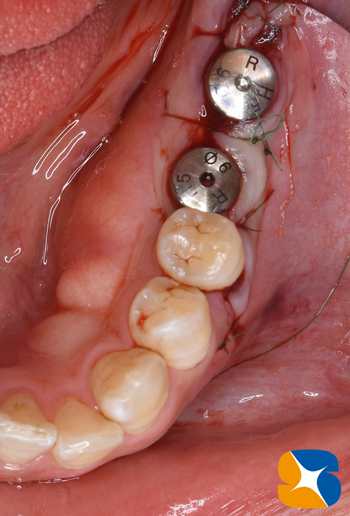

左下のインプラント予定部。

切開して開けてみると、2ヶ月前の抜歯跡が見受けられた。しかし

当院では骨の再生治療をインプラント移植時に同時進行で施しているので、全く問題はありません。

骨のない所に人工骨のβ–TCPを添加して、本物の骨に置換するのを待ちます。